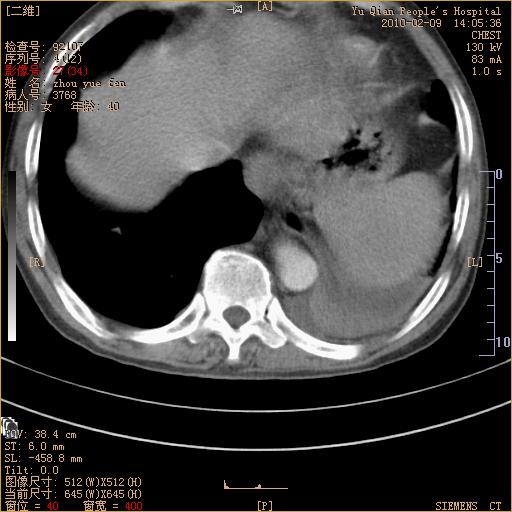

男性,73岁,咳嗽咳血数天,诊为肺ca伴左肺下叶后段阻塞性炎症、肺不张妥否?

左下肺中央型肺癌伴结段形肺不张,左侧胸腔积液,纵隔内见部分增大淋巴结(反应性增生或转移)

1、左肺下叶后基地段肺癌伴阻塞性炎症,左下肺门淋巴结转移。2、左侧胸腔积液。